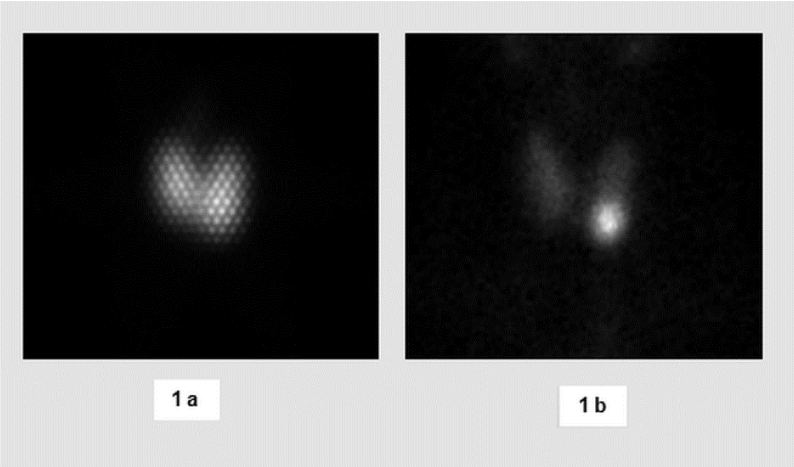

The planar Tc-99m-O4- and I-131 scintigraphies of the thyroid were first visually analyzed and compared to each other on a computer monitor by two experienced specialists in nuclear medicine in consensus on the basis of the different grey intensities (Figure 1).

Figure 1: Patient 24, varying maximum activity in visual comparison of I-131 scintigram (1a) with the Tc-99m-O4-scintigram (1b). Grid image in Figure 1a highlighted by the use of a high-energy collimator.